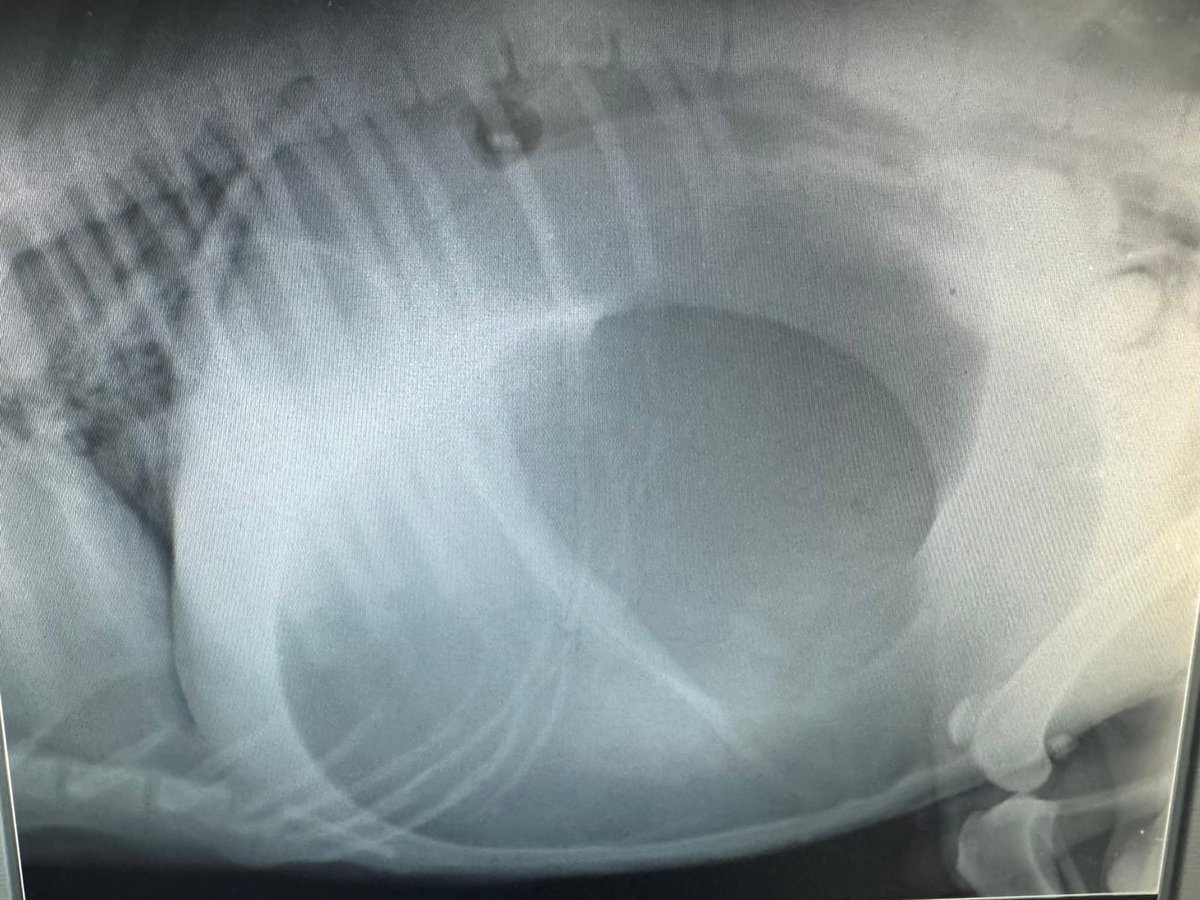

"Milla“:

Hochgradige Flüssigkeitsansammlung in der Bauchhöhle aufgrund einer Herzwurmerkrankung. Wir werden Milla übernehmen und ihr alle erforderlichen Therapien zukommen lassen. Sie soll nie mehr in diese Situation kommen müssen.